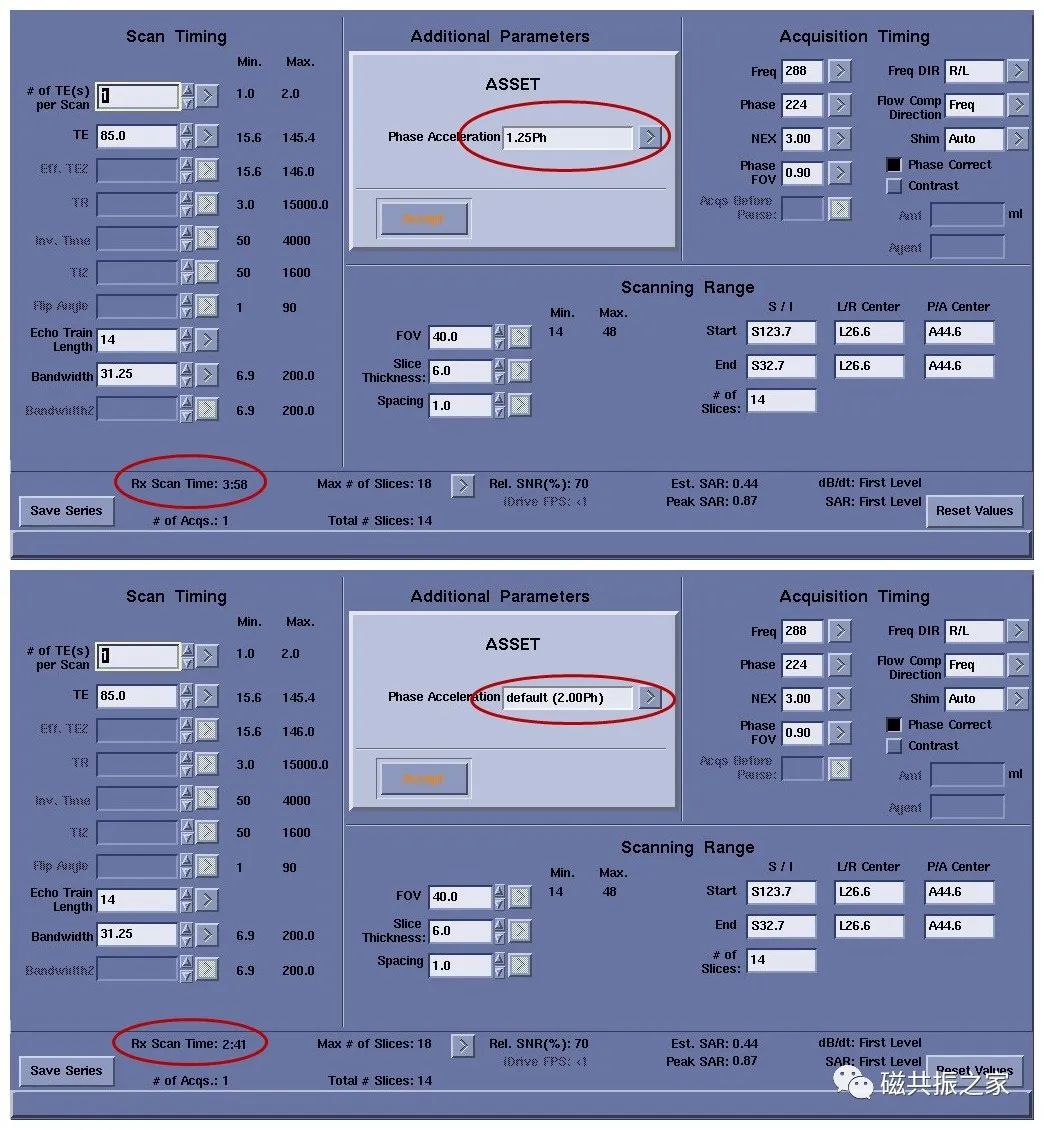

四、改变线圈

优良的线圈是获得高质量图像的关键。使用相同的时间,专用线圈获得的图像不管是信噪比还是对比度都比通用线圈优秀。同样使用多通道并行采集线圈,在获得同等信噪比的情况下,多通道线圈比单通道成像更快。

使用并行采集技术能明显的加快扫描速度,其扫描的速度与加速因子息息相关。如加速因子为1.25时,扫描时间为3:50,加速因子为2时,扫描时间为2:41。